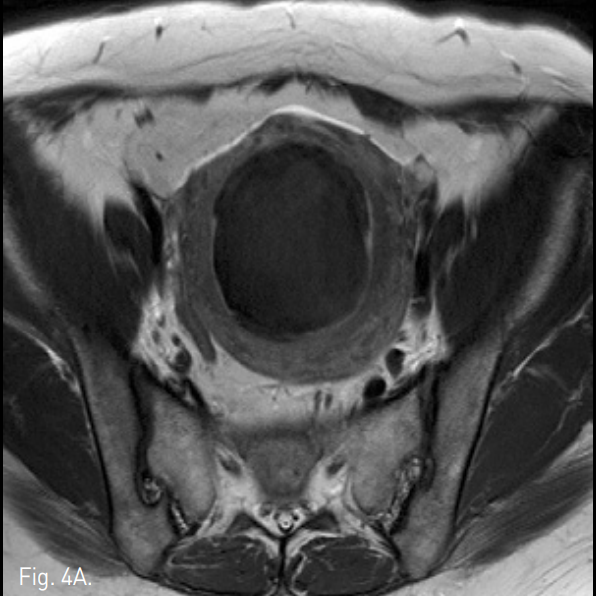

Fig. 4

A-C. Three months follow-up T2-weigh ted transverse (A), coronal (B), sagittal (C) MR images show a huge mass of low signal intensity.

D. Three months follow-up T1-weighted MR image with contrast enhancement shows a non-enhancing uterine mass.